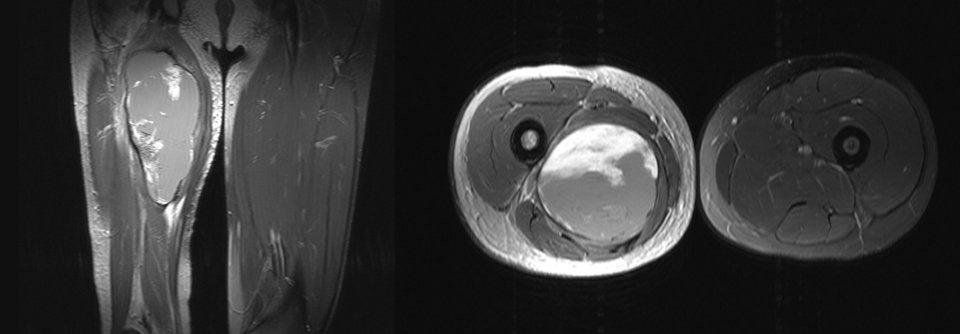

Die Auswertung ergab eine Differenz von 7,6 Punkten für die gezielte Kräftigung des vierköpfigen Oberschenkelmuskels. Mit dem „Hüfttraining“ wurden 7,0 Punkte erreicht. Die erzielte Verbesserung war zwar in beiden Gruppen statistisch signifikant, vom Effekt her allerdings sehr klein. Zum Nachweis eines klinisch relevanten Nutzens hätten die Teilnehmer eine Veränderung um mindestens acht Punkte erreichen müssen.

Somit haben die beiden Übungsformen einen geringen, aber ähnlichen Einfluss auf den patellofemoralen Schmerz. Deshalb kann man den Patienten freistellen, ob sie lieber Hüfte oder Knie trainieren wollen, meinen die Studienautoren um Rudi Hansen von der Universitätsklinik Kopenhagen.